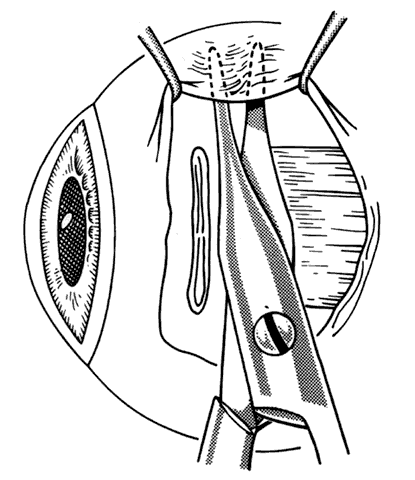

When approaching the superior and lateral rectus muscles that have had previous surgery, care should be taken to identify the superior oblique tendon and the inferior oblique muscles respectively. One should carefully free up attachments of these structures to the rectus muscle so that a normal anatomic relationship between the rectus and oblique muscles can be re-established. Frequently, the lateral rectus muscle will have adhesions to the orbital surface of the inferior oblique muscle as it passes underneath the lateral rectus. There is a propensity for the inferior oblique muscle to be drawn up into the insertion during resection procedures.37 When this occurs, the inferior oblique and lateral rectus muscle must be separated, and the inferior oblique muscle should be repositioned into its normal anatomic position (Figs. 30 through 33).

Fig. 31. The inferior oblique muscle has been incorporated into the insertion of the right lateral rectus.

Fig. 32. Sharp and blunt dissection is used to “free up” the inferior oblique muscle from the scleral side of the lateral rectus.